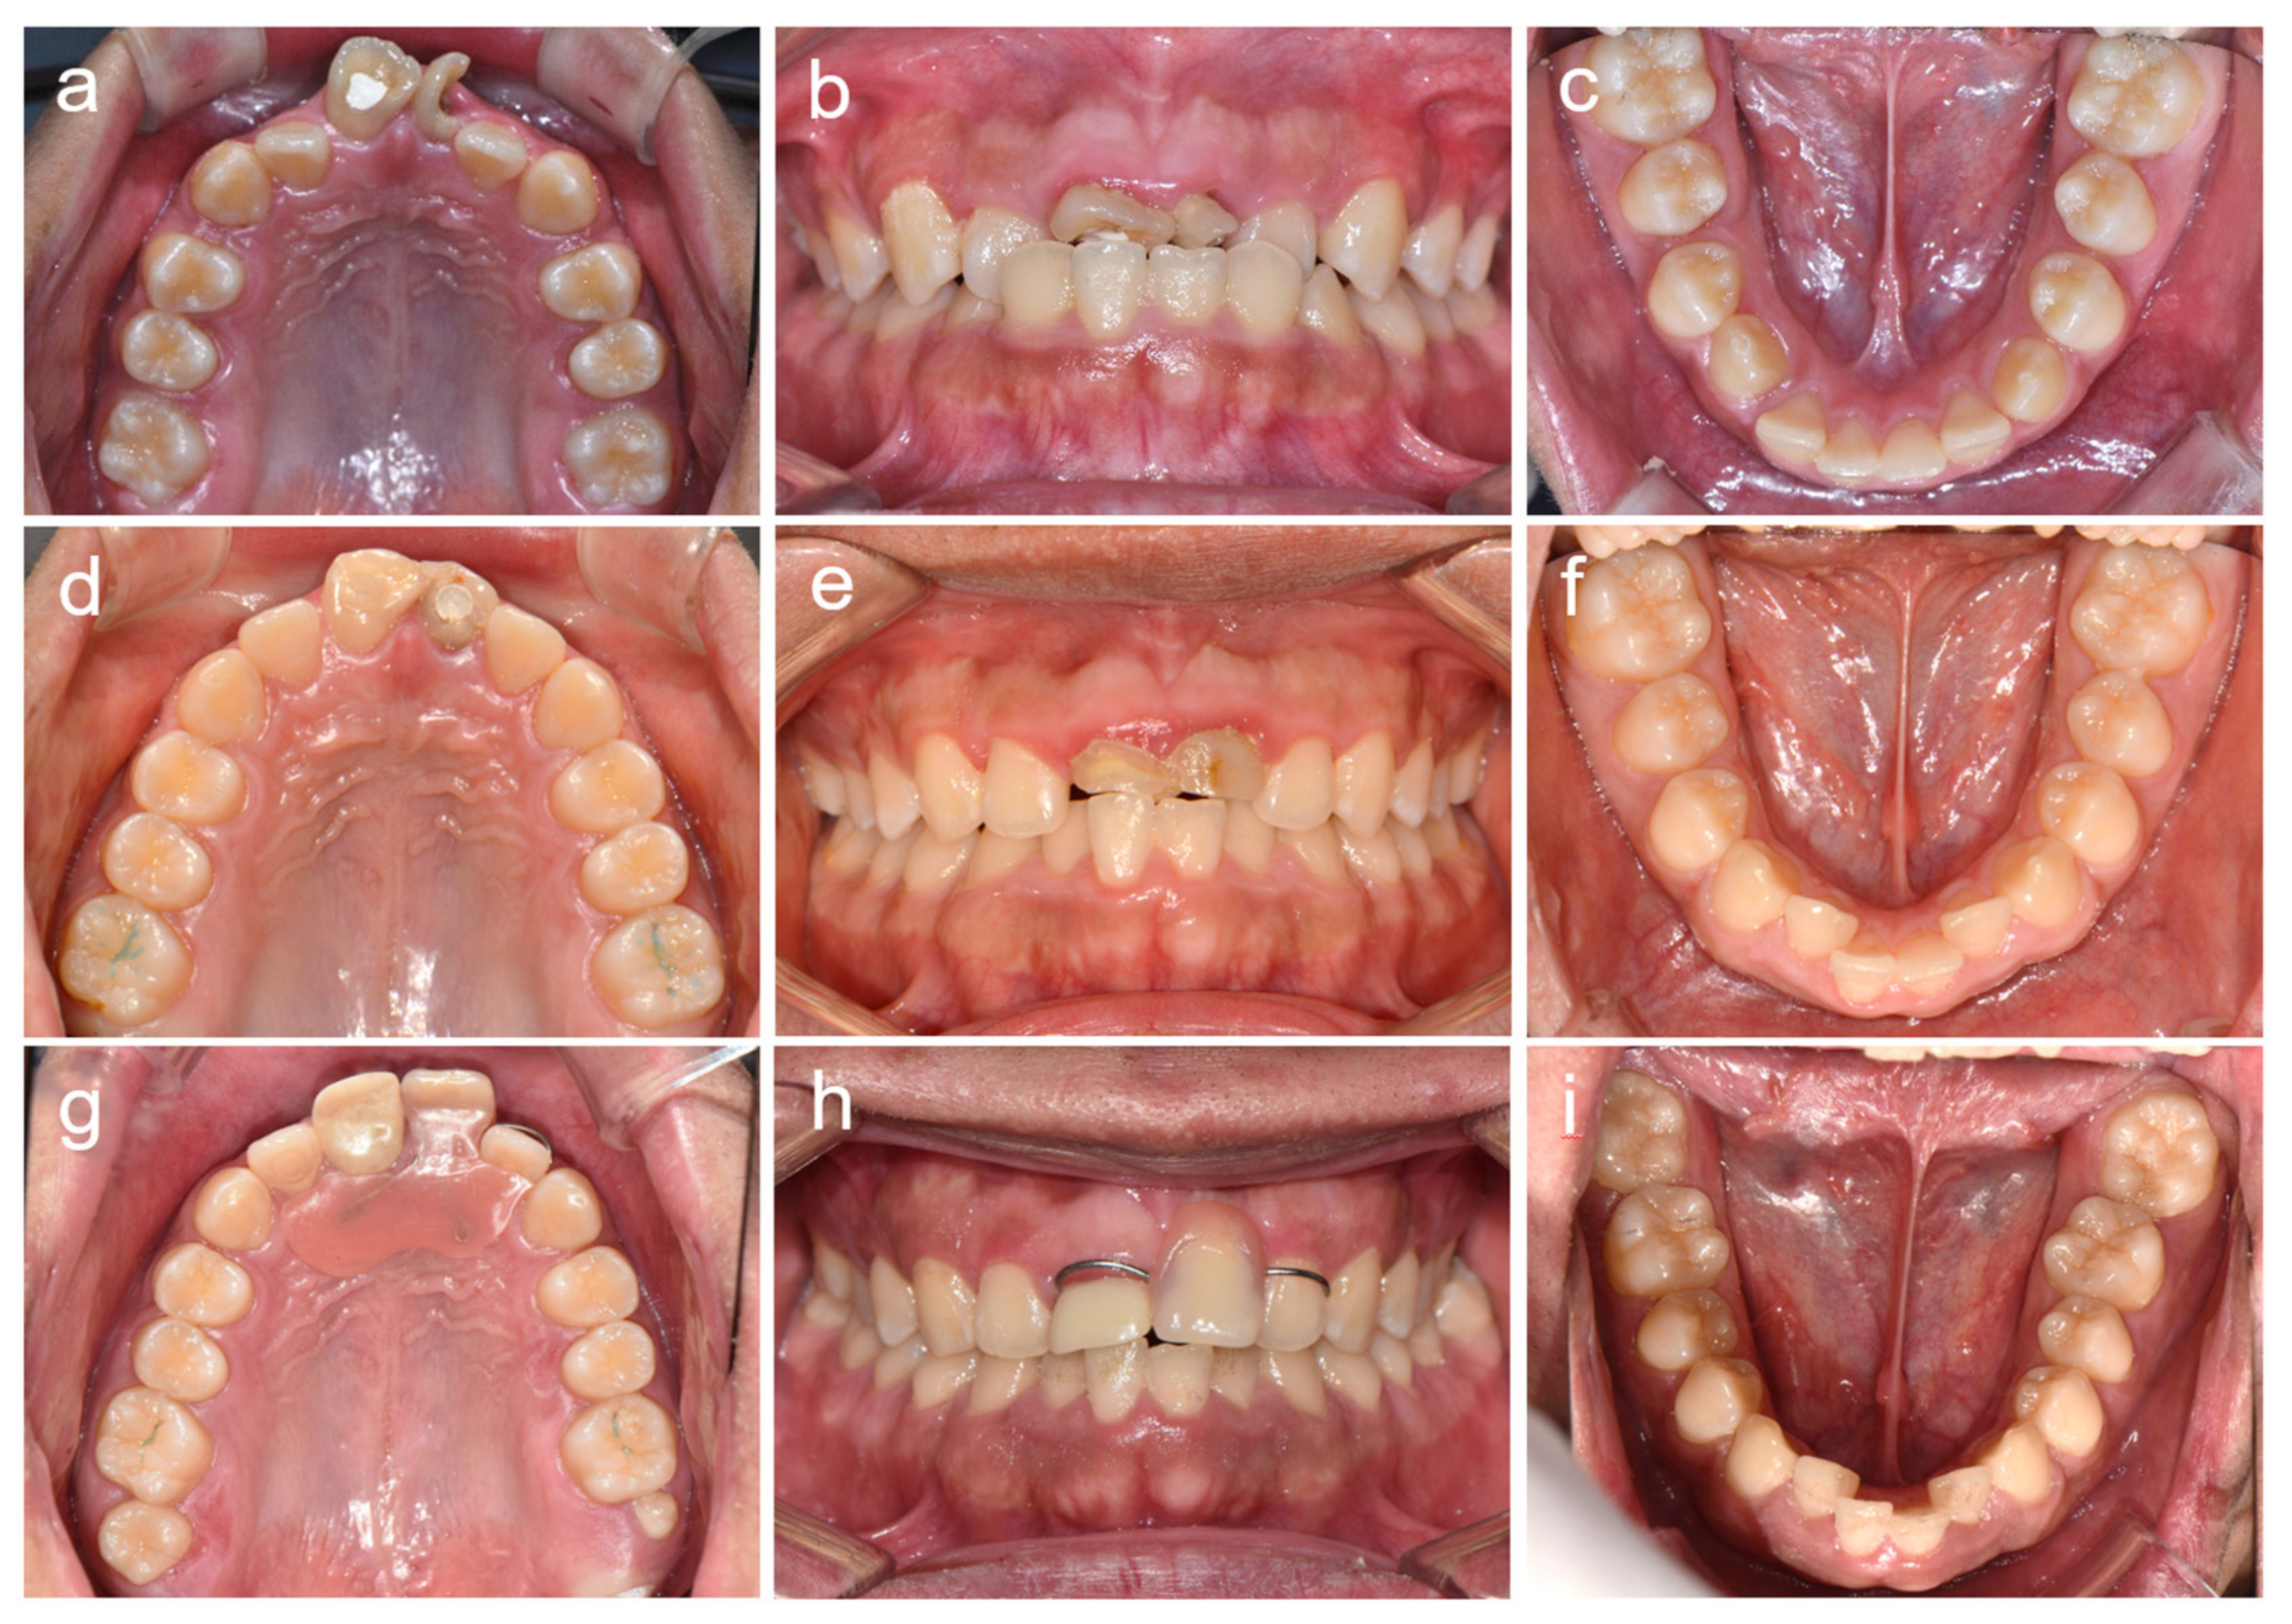

2. Cases

2.1. Case 1

2.2. Case 2

2.3. Case 3

2.4. Case 4

2.5. Case 5